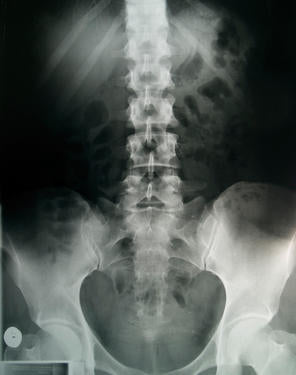

Bone density testing is based on a special x-ray method called densitometry. The method of testing is referred to as Dual X-ray Absorptiometry (DXA). DXA testing arrived on the scene in the early 90 and by 1994 a new criteria was accepted by the World Health Organization to diagnosis osteoporosis and osteopenia (low bone density). The cut off diagnosis was determined to be 30% less bone density than an average 30 year old. Once this diagnosis was set in motion doctors around the world thought that they needed to treat, not only those who had osteoporosis, but also osteopenia, which is 12 to 24% less bone density than an average 30 year old. This new testing helped identify those at risk of fracture and treatments that saved lives and it also led to thousands of people taking medications who had little to no risk of fractures.